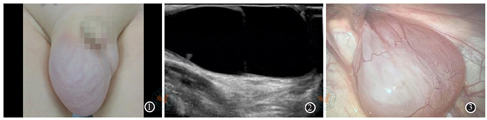

腹阴囊鞘膜积液6例,例3和例6患儿出生后即发现,手术年龄分别为20月、40月。除例6患儿临床诊断腹股沟斜疝外,其余5例临床均诊断精索鞘膜积液。查体可见腹股沟至阴囊区体积大、张力高囊性包块,透光实验阳性(图1)。例3~例6患儿超声提示腹股沟区睾丸后上方低回声包块并延伸至腹腔,积液量多,有时可见分隔(图2)。腹腔镜术中见例6患儿腹腔内囊性包块位于精索后外侧腹膜后,囊膜为腹膜组织,排尽液体后囊膜不能回纳至鞘突管(图3),其余5例患儿囊性包块均自内环口处脱出(图4)。例1和例3患儿先将腹腔内包块还纳至鞘突管,再行鞘状突高位结扎,最后经阴囊抽出积液。其余4例患儿先穿刺针刺破腹腔内囊性包块,将囊液排尽,再囊膜还纳至鞘突管后,行鞘状突高位结扎。例4和例5患儿腹腔内包块液体排尽,高位鞘状突结扎后,仍经阴囊分别抽出15 ml、20 ml液体。所有患儿常规随访,术后3个月复查超声,随访10~24个月,无再次出现症状。